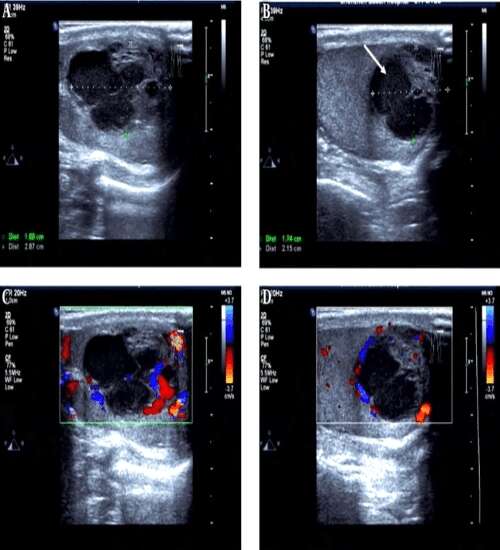

Scrotal Colour Doppler ultrasound is an imaging test that is used to view the scrotum(the flesh-covered sac that hangs between the legs at the penis base and contains the testicles) It uses sound ways to produce images of the male reproductive organs (testicles) and its surrounding tissues.

Doppler scan for scrotum is a painless, rapid, non-invasive and safe technique that is used for the evaluation of various pathological conditions affecting the testicles or the scrotum.

• More detailed visualization of scrotum and testicles.

• Provide real-time speed and direction of blood flow in scrotal or testicular blood vessels.